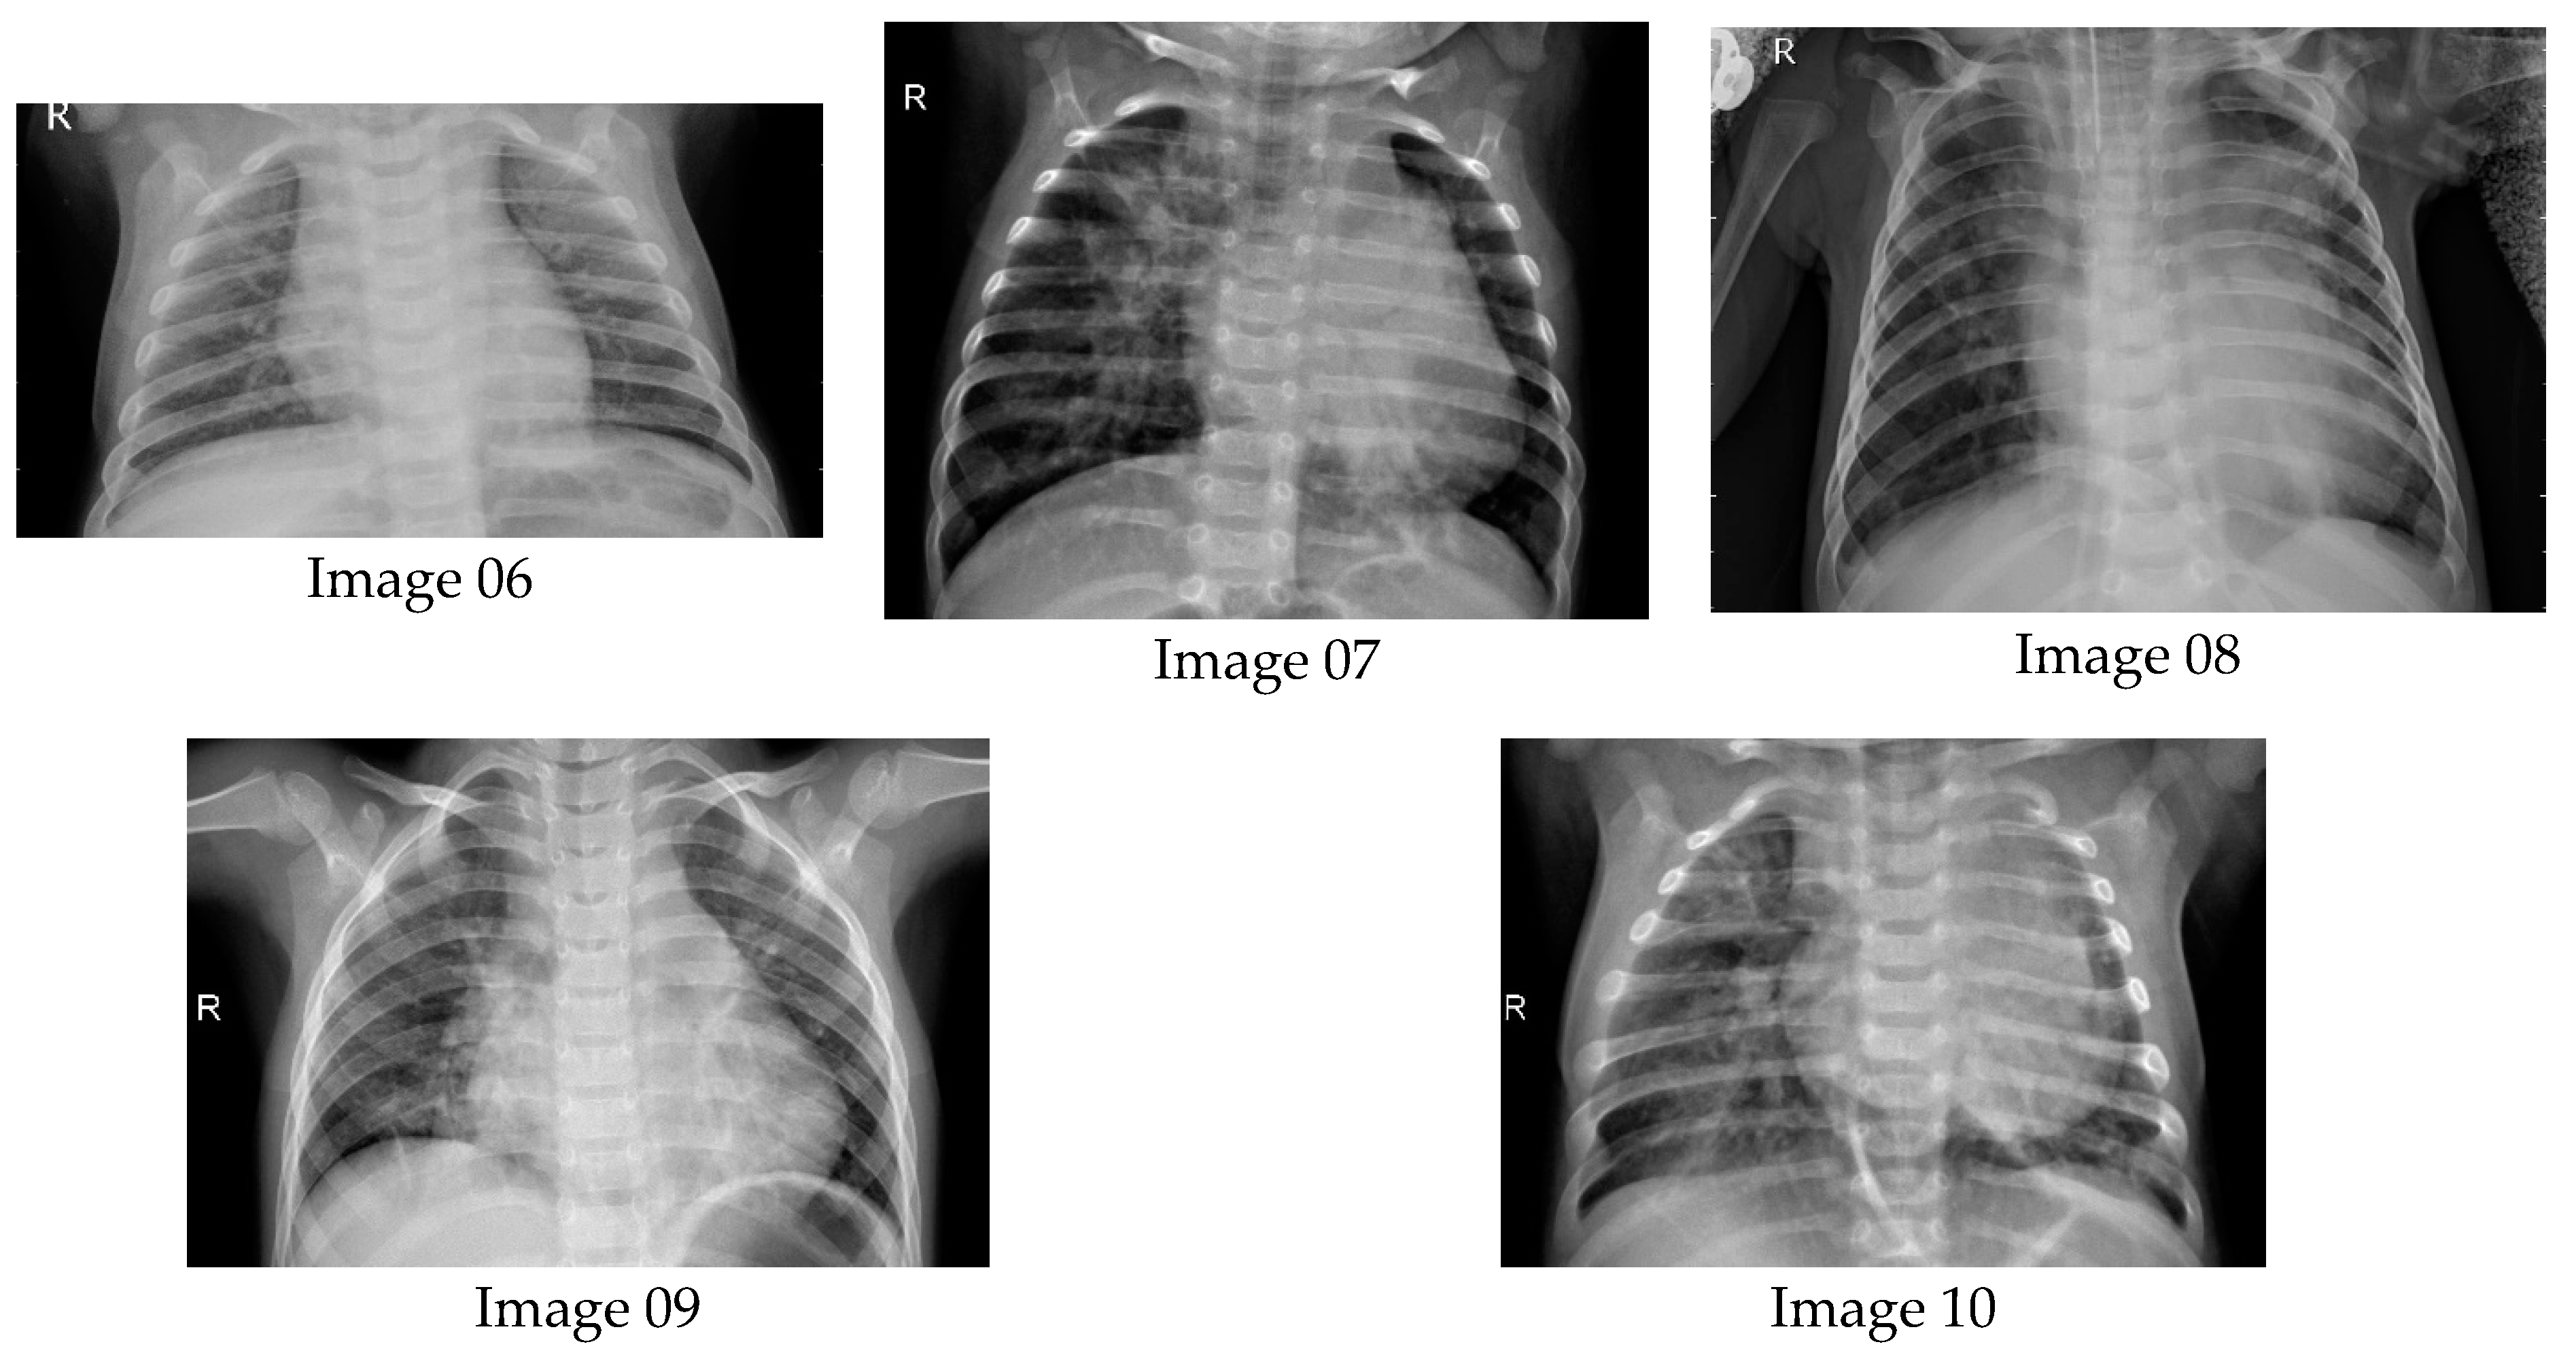

6.1. Results from Lung Radiographs

- Kaggle. Chest X-ray Images (Pneumonia). 10 February 2018. Available online: https://www.kaggle.com/datasets/paultimothymooney/chest-xray-pneumonia (accessed on 24 August 2023).